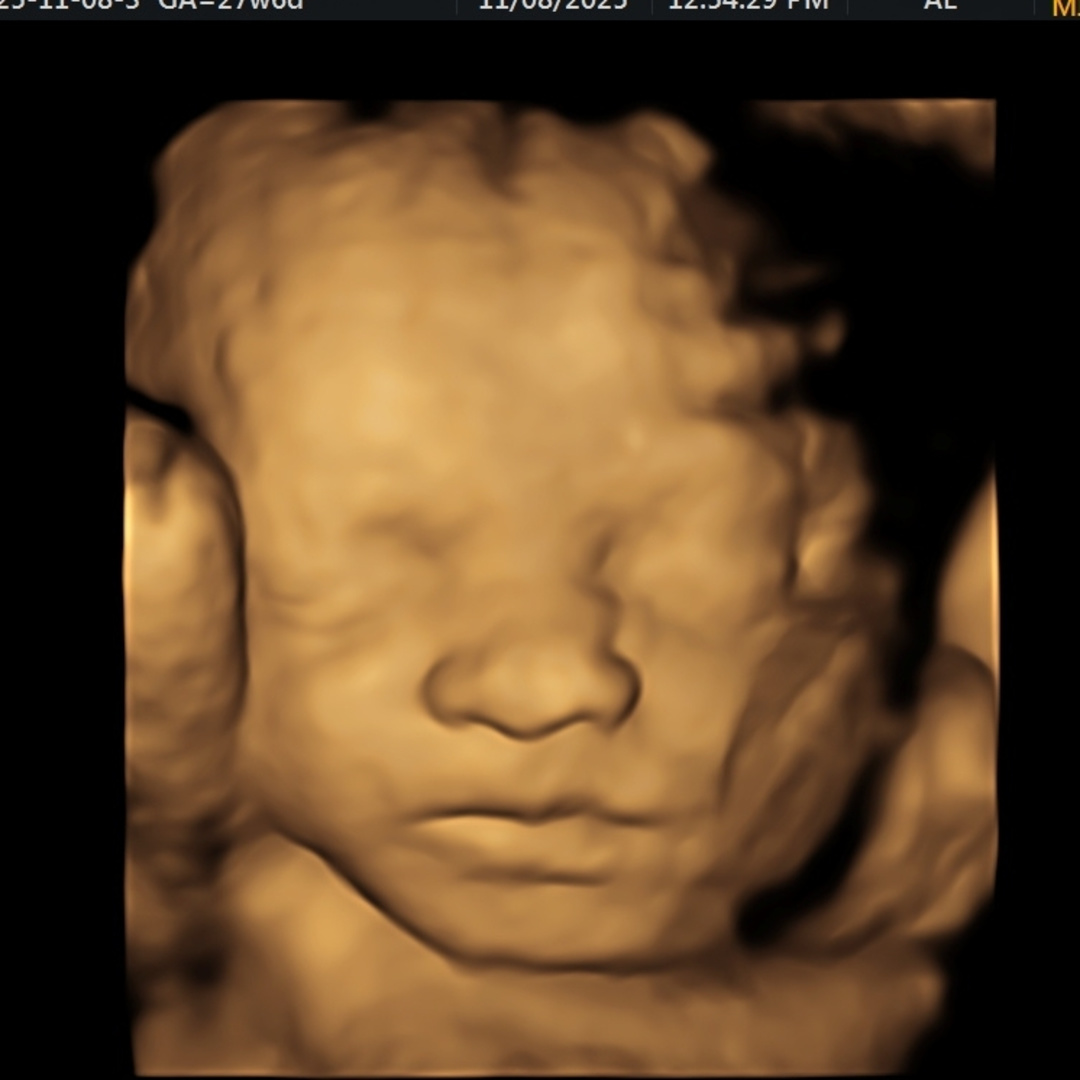

Sam & Chris Baby Registry

Thank you all so much for your support as we prepare to bring our little girl into the world🩷

Our Sweet Olivia